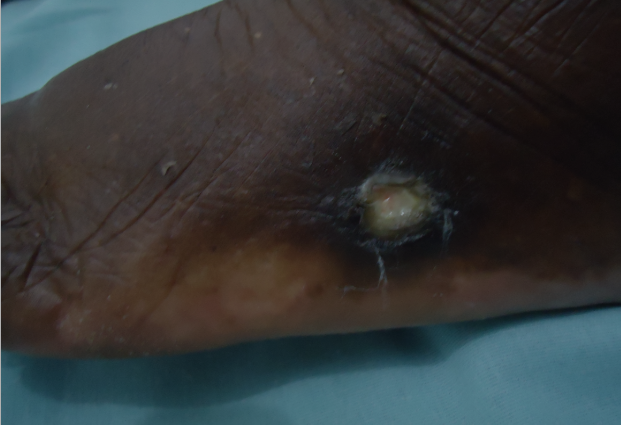

Chegando lá, deparou-se com muitos pacientes que eram portadores de lesões ulceradas crônicas nos membros inferiores, as Ulceras Varicosas.

Após os problemas políticos aos quais mencionamos ao ir clinicar em Minas Gerais encontrou o que faltava: Muitos pacientes com o problema e muito conhecimento popular que somado aos conhecimentos científicos que tinha chegou-se a uma conduta que podemos chamar de CONDUTA ÚNICA, para o tratamento destas lesões, que independente do tratamento ou tratamentos já realizados e o tempo do inicio das lesões. O tratamento realizado com esta CONDUTA ÚNICA em apenas 15 ou 30 dias, cura-se as lesões Varicosas “pele-a-pele”. Mesmo pacientes com fatores complicativos como o caso de “Pés Diabéticos”.

ANTES E DEPOIS

Confira os resultados reais de nossos pacientes